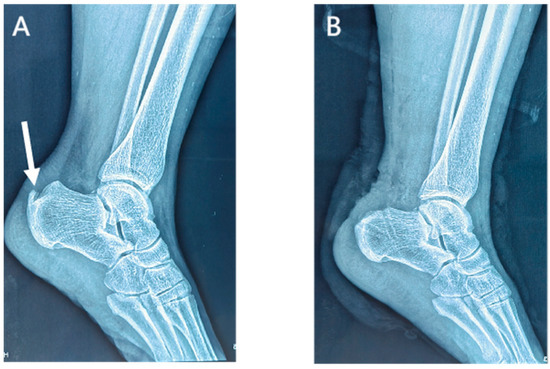

Lateral radiographs of the ankle 1 day postoperatively showed the complete removal of the calcific lesions in the Achilles tendon (Figure 3 and Figure 4). No loosening or fracture of the anchors occurred during the follow-up. All the surgical wounds healed well with no infection, scar, or dehiscence. No severe complications occurred, such as sural nerve injury, saphenous vein injury, or venous thrombosis. No patients experienced Achilles tendon rupture, contracture, or adhesion. There was no significant difference in the range of motion between the affected ankles and the contralateral ones (dorsiflexion: 23.7 ± 1.5 vs. 23.8 ± 1.9 degrees, p = 0.503; plantar flexion: 38.8 ± 2.2 vs. 39.3 ± 2.1, p = 0.080). At the last appointment, all 25 patients were asymptomatic and had returned to their pre-injury levels of activity and mild sports.

Figure 4.

Preoperative (A) and postoperative (B) lateral radiographs of the ankle in the suture bridge group. Arrow, a calcific lesion in the Achilles tendon.